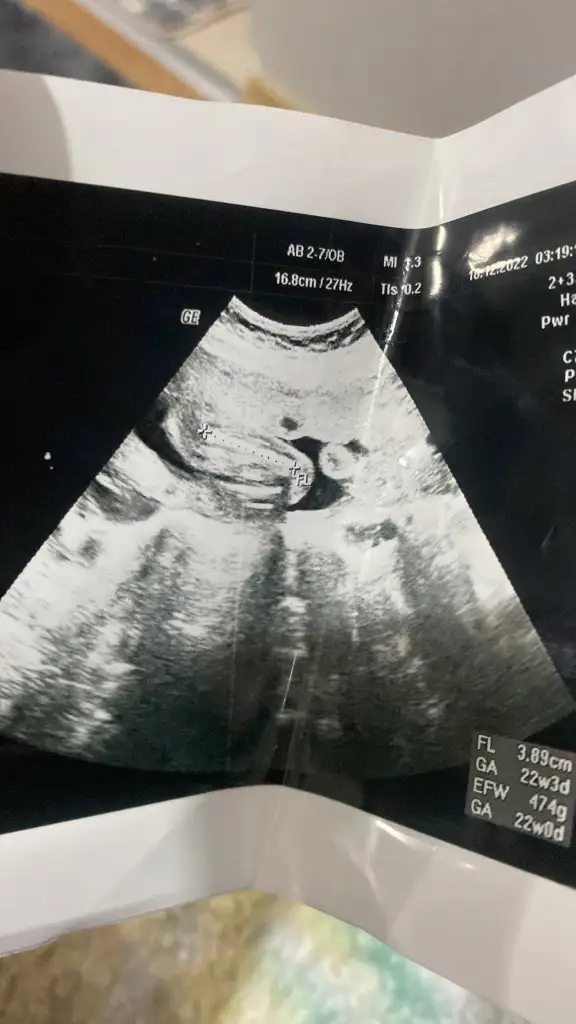

Şimdi de erkek denildi ben hâlâ cinsiyet ne olduğunu anlamadim😂

Kızlar 13+4 haftalıkken doktor çok kararsız kaldı ama kıza benziyor dedi hazırlık yapma dedi ben erkek hissediyorum bana da bakabilir misiniz?

Bu cuma tekrar gitcem erkek derlerse gine erkektir büyük ihtimal ama ayrintiliya girmek isterim öyle daha net olur